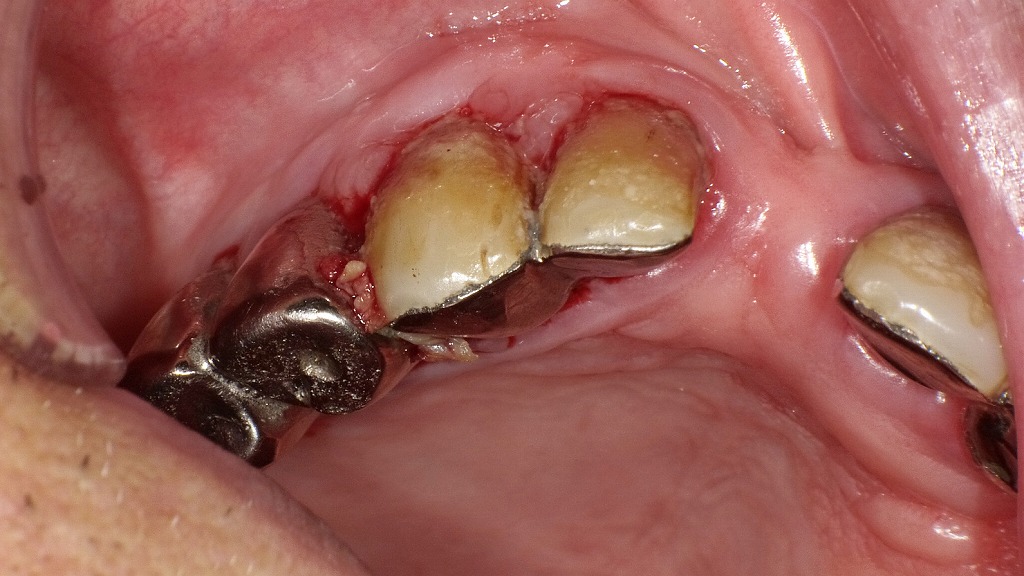

上顎は無歯顎となり、下顎には重度の虫歯や歯周病が認められる状態です。歯の喪失や残存歯の機能低下は、咀嚼能力の低下や食事内容の偏りを招き、口腔機能全体の衰えにつながります。このような状態が進行すると、発音・嚥下・栄養状態にも影響し、オーラルフレイルの重要な背景因子となります。適切な補綴治療と歯周管理、早期介入が予防と改善の鍵となります。